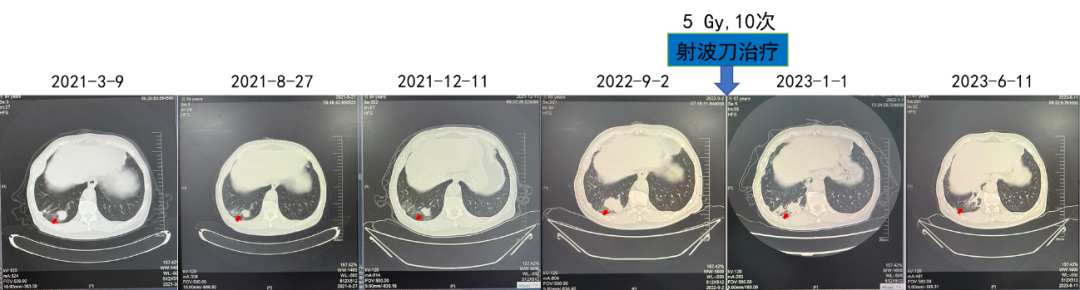

第三阶段:靶免联合+射波刀

2021.03阿昔替尼5mg BD+帕博利珠单抗200 mg+射波刀

疗效:肺部病灶疾病稳定(4年)。对侧肾上腺病灶部分缓解(4年)。

(射波刀治疗)